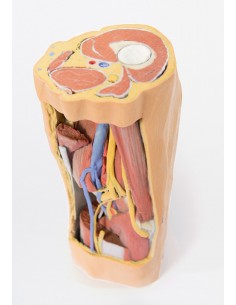

3D Anatomy 1.0 - Extremidades inferiores

Fosa poplítea con distal del muslo y pierna Erler Zimmer 3D anatomy Series MP1820

3D Anatomy 1.0 - Extremidades inferiores

Disección profunda de la fosa poplítea Erler Zimmer 3D anatomy Series MP1830